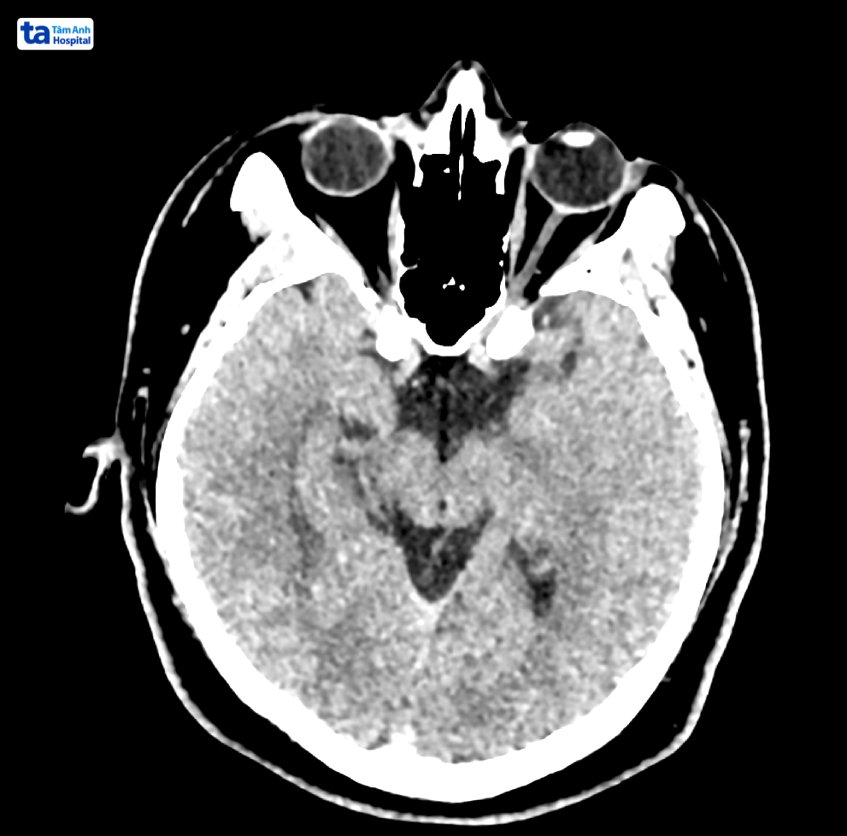

Chụp CT não là một kỹ thuật chẩn đoán không xâm lấn, sử dụng tia X quét xung quanh não để cho ra hình ảnh chi tiết về cấu trúc não và các bệnh liên quan, đặc biệt là ung thư não. Ung thư não thường rất khó chẩn đoán sớm vì không có dấu hiệu rõ ràng, do đó, chụp CT não có thể được dùng để phát hiện ung thư não ngay cả khi khối u còn rất nhỏ. Ngoài việc chẩn đoán qua hình chụp CT, bác sĩ thường kết hợp với các phương pháp chẩn đoán bổ sung như MRI, sinh thiết hoặc xét nghiệm tế bào… để đưa ra chẩn đoán chính xác nhất.

Chụp CT não là chẩn đoán hữu ích giúp bác sĩ xem xét đánh giá các vấn đề hay bất thường, chấn thương ở não hoặc các tình trạng khác liên quan đến não. Chụp CT não còn có thể giúp theo dõi quá trình hay hiệu quả điều trị.